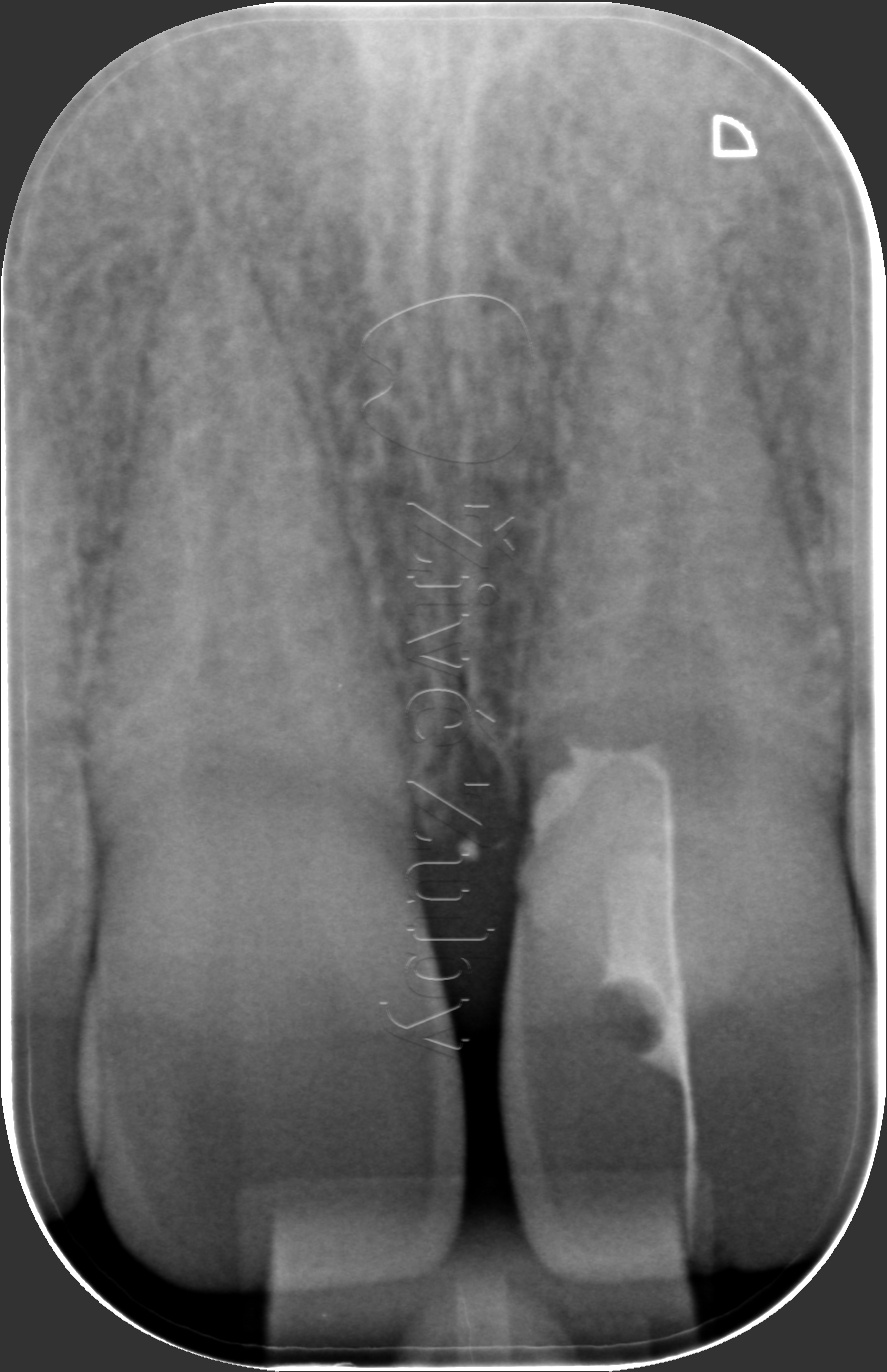

Fraktury zubů

(nekomplikované, komplikované, pulpotomie, … )

Výchozí stav  ——-  Kontrola po 2 letech